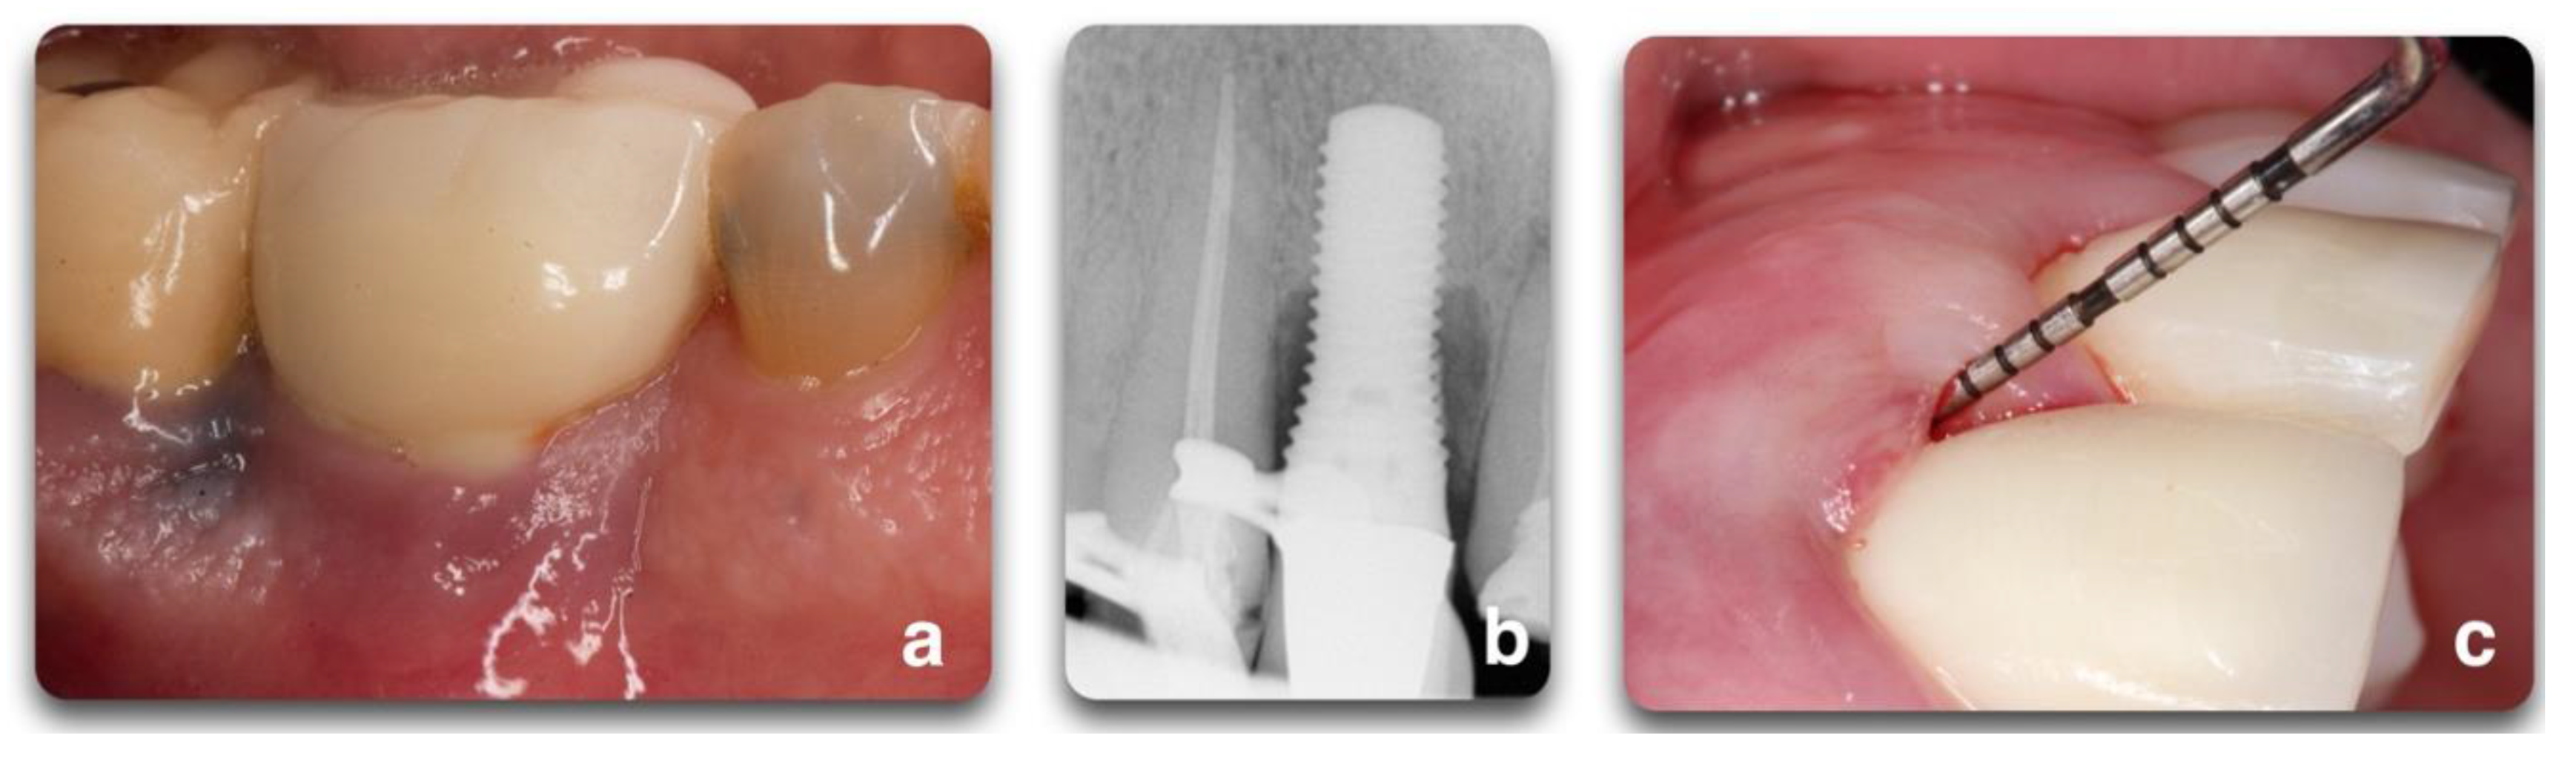

Figure 10.

Regenerative peri-implant therapy for implant area #22. (a,b) Pre-operative clinical and radiographic presentation. BoP, SUP, PD > 5 mm. (c) Defect configuration after the elevation of the full-thickness flap. (d) Decontamination with rotating titanium brushes, saline, and chlorhexidine rinse, and 2 min of tetracycline hydrochloride soluble powder applied to the implant surface. Bone grafting application and flap closure around existing locator abutment (LOCATOR Astra Tech EV Overdenture Abutment © Dentsply Sirona); (e,f) 12 months post-operative clinical and radiographic outcomes. To be noted is the partial fill of the intra-bony defect with a residual supra-crestal fixture.